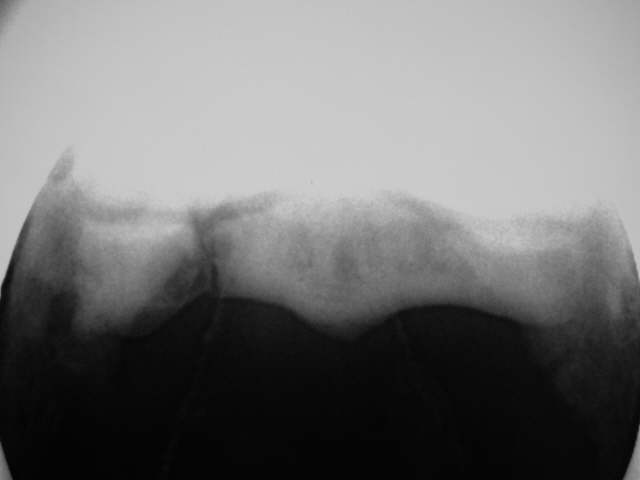

Skyline Befunde

Alte Strahlbeinfraktur Röntgenklasse IV